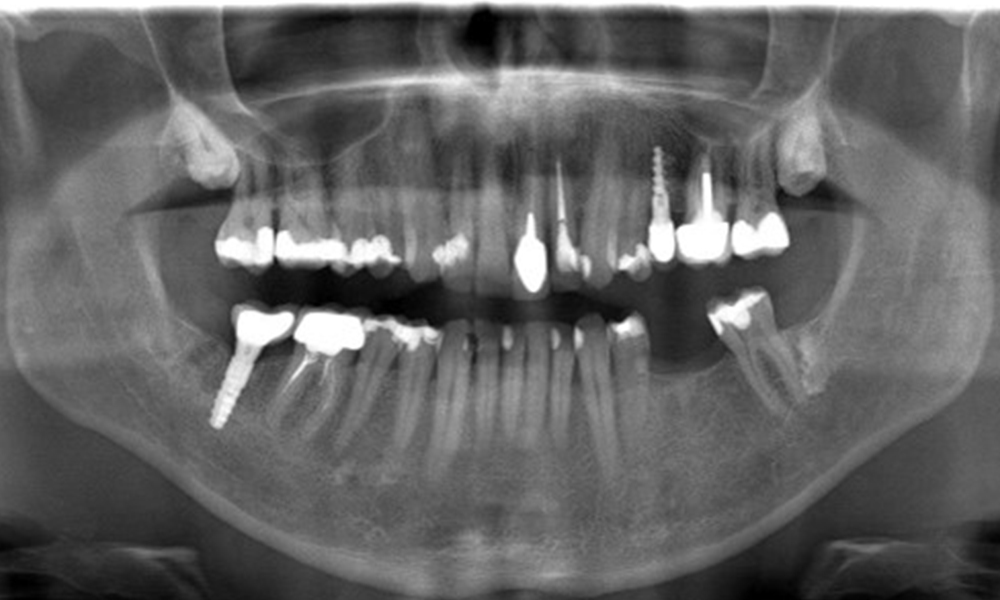

In the medical history, the 55-year-old patient states that he has no systemic disease and is not taking any medication. The patient’s lifestyle is similarly unremarkable. The patient has a few tooth restorations and two implants (2nd and 4th quadrants). On the basis of current findings, gingivitis is identified in an otherwise stable periodontal condition on the reduced periodontium (stage III, grade A).

Previous treatments: dental restorations (non-precious metal/ceramic blend), two implants (2nd, 4th quadrants)

The patient has no particular risk factors with specific dental implications. The key factor, therefore, is the requirement in terms of oral health. In this respect, good oral health is evident with stable, reduced periodontium. Should evidence of an increase in probe depth compared with the baseline, combined with diffuse bleeding, be found at a check-up appointment, diagnosis using X-ray imaging (dental X-ray) should be undertaken in order to identify peri-implant bone loss at an early stage and intervene accordingly.